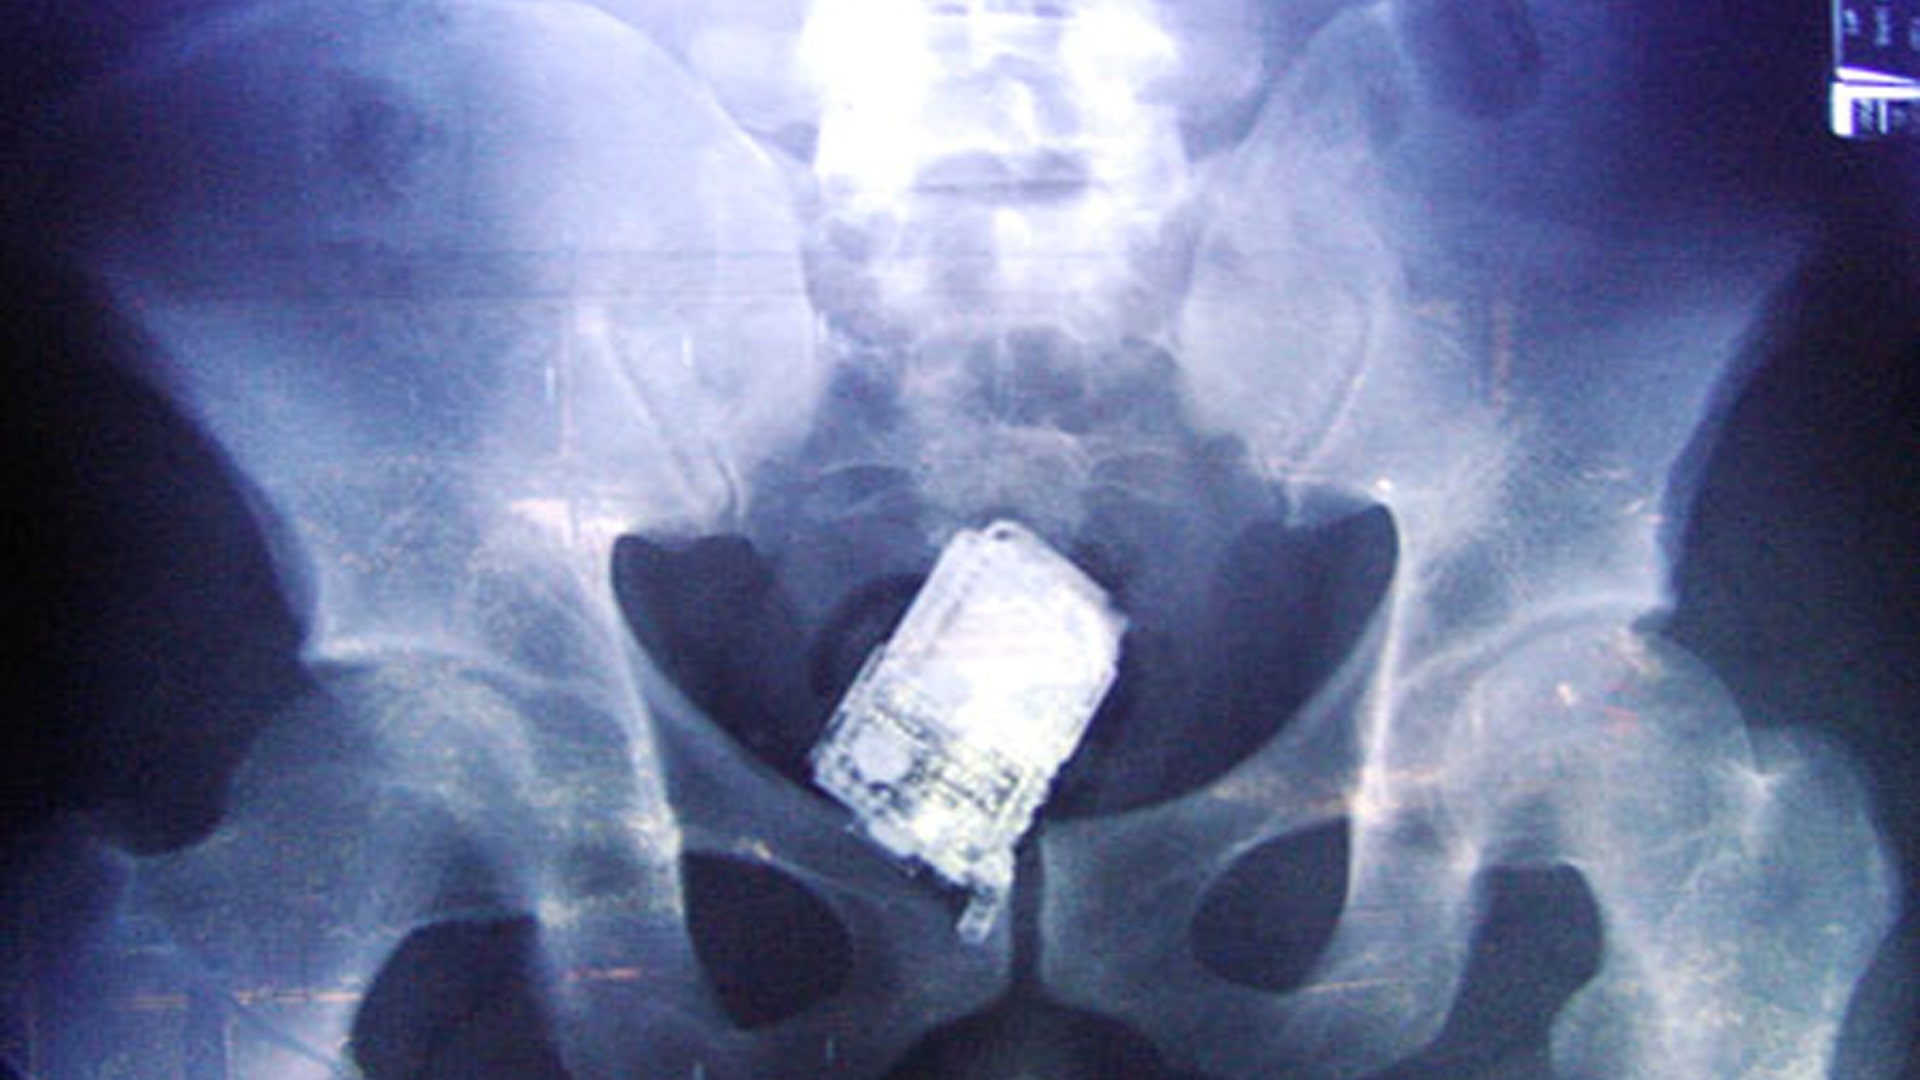

Xiao Wei, 16, who was attacked in a dispute over the video game he was playing, was able to walk into the emergency room entrance of Jillin University with the 10-inch knife still lodged in his head. An operation to remove the blade took more than two hours. X-rays and CAT scans revealed that no main arteries or nerves were damaged.read more![Phone in Stomach]()